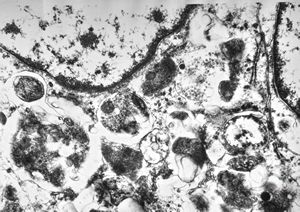

F, 24y. | molluscum contagiosum … virions